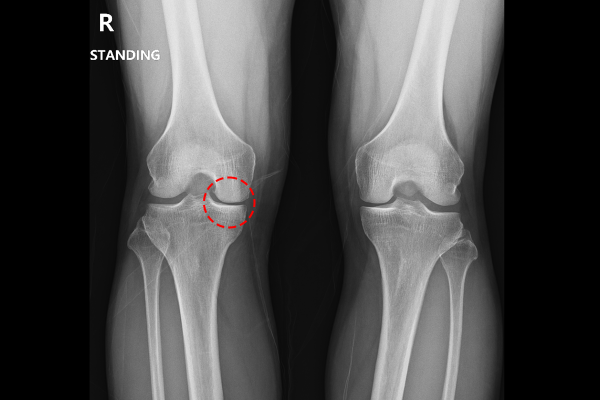

62세 남성 환자분께서 우측 무릎 통증으로 내원해주셨습니다. 무릎에 통증이 발생한지는 약 2년 정도 되었다고 말씀하시며, 2년간 꾸준히 동네 다른 병원에 다니시며 무릎 주사 치료를 받았다고 하셨습니다. 하지만 증상이 호전되지 않아 정밀검사와 근본적인 치료를 위해 저희 병원을 찾아오시게 되었다 말씀하셨습니다.(현재 무릎 안쪽이 많이 불편하다고 하셨습니다.)

환자분의 무릎 상태를 자세히 파악하기 위해 X-RAY 사진을 확인했을 때, 무릎 안쪽 관절이 닳아서 바깥쪽에 비해 많이 좁아져 있는 3기 정도의 무릎 퇴행성 관절염이 확인되었습니다.